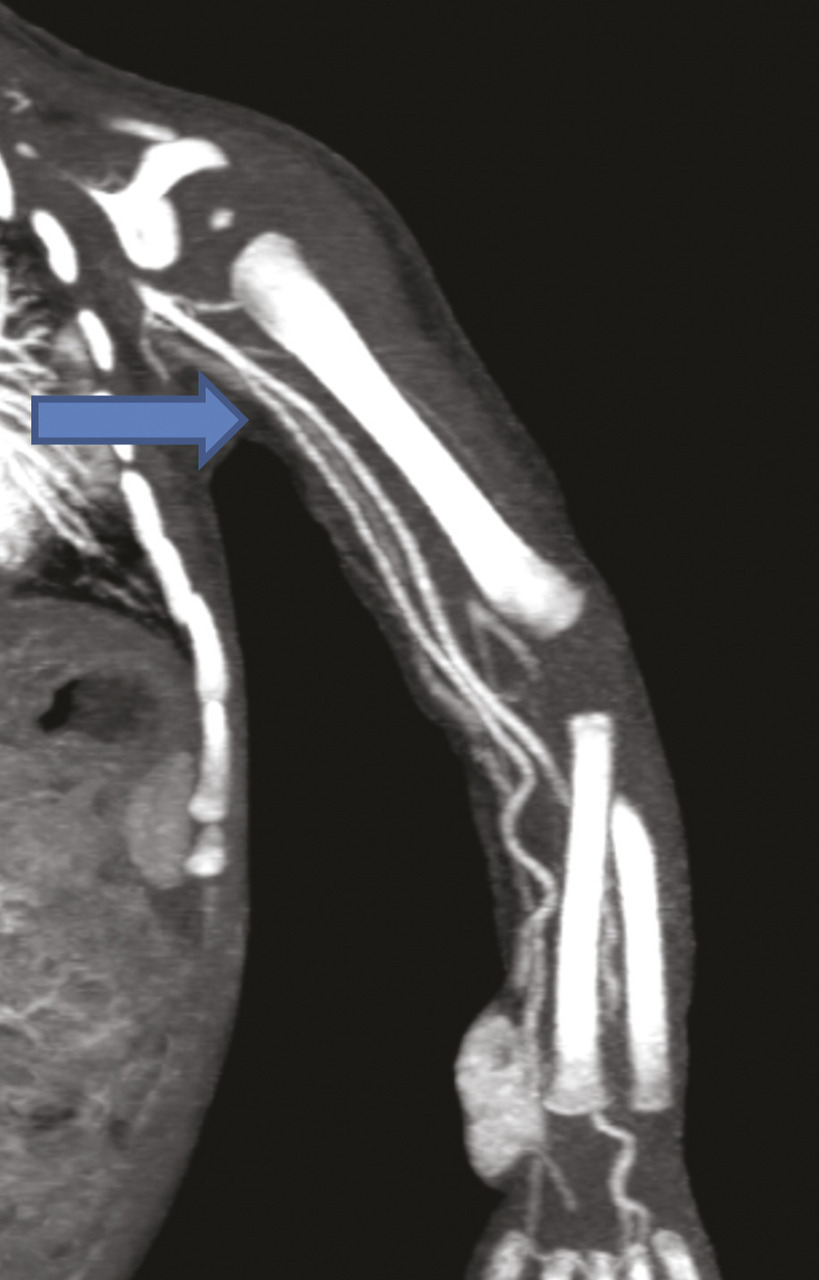

Ce nourrisson de 11 mois était hospitalisé pour l’exploration d’une masse à l’extrémité inférieure de l’avant-bras. À l’échographie, on notait une formation tissulaire hypervasculaire au Doppler couleur, motivant un complément d’investigations. L’imagerie par résonance magnétique étant techniquement difficile à réaliser, un angioscanner a été demandé, qui montrait (fig. 1 et 2 ) une tumeur vasculaire à développement essentiellement sous-cutané respectant les structures musculaires et osseuses. Il mettait en évidence une variante anatomique : une origine haute de l’artère radiale sans cross-over avec l’artère cubitale.

L’artère radiale a une importance médicale majeure : elle permet le monitoring de la pression artérielle en anesthésie et réanimation, elle sert de greffon en chirurgie coronarienne, et constitue un abord essentiel dans les fistules artérioveineuses d’hémodialyse. Selon les études,1 la prévalence estimée de l’origine haute de l’artère radiale, appelée aussi artère radiobrachiale, varie de 4,67 à 15,6 %. Cette particularité est le plus souvent unilatérale, sans prédominance de sexe ou de côté rapportée à l’heure actuelle. Elle peut prendre naissance à plusieurs niveaux, depuis l’artère axillaire jusqu’à l’artère humérale. Le cross-over cubital correspond à une artère anastomotique faisant communiquer l’artère cubitale avec l’artère radiobrachiale. Ce cross-over a été observé dans 17,8 % des cas de naissance haute de l’artère radiale.2 Compte tenu de son importance pour les abords vasculaires, il est important de connaître les variantes anatomiques de l’artère radiale.